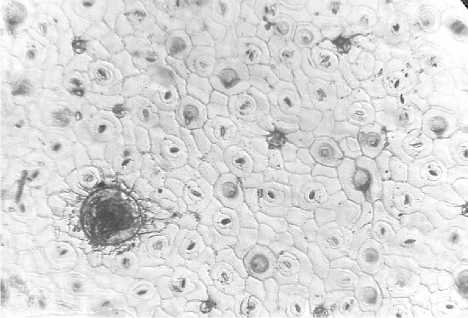

На поверхности чашелистиков наблюдаются многочисленные простые двухклеточные волоски с бородавчатой поверхностью, между ними встречаются головчатые волоски с двухклеточной ножкой (рис. 4а).

По всей поверхности лепестков в большом количестве идентифицируются многочисленные крупные округлые эфирномасличные железки с коричневым содержимым. Эфирномасличные железки округлые, расположены по радиусу и состоят из восьми выделительных клеток. Также на поверхности лепестков в большом количестве присутствуют одно-, двухклетчатые бородавчатые волоски и редко встречаемые голововчатые (рис. 4б).

б

а

Рис. 4. Венчик (а — извилистые клетки; б — эфирномасличные железки и головча- тые волоски с двухклеточной ножкой)